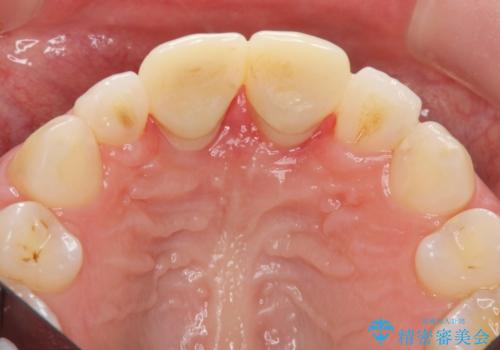

その後、マージンが舌側が深い状態だったため、歯ぐきの手術(歯周外科処置:APF)を行ってから最終的なセラミックを装着しました。

終了時